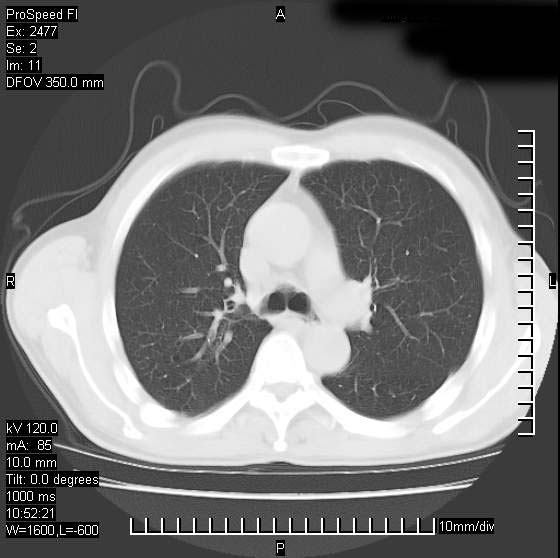

以下是引用天南地北在2007-10-9 14:29:00的发言:[br]1:右上肺结核[br]2:右肺下叶肿块:不支持肺癌,首先考虑炎性病变-肺脓疡可能性大[br]理由:1:临床病史支持,肺脓肿症状不明显应该是不规则服药造成。[br] 2:肿块边缘模糊,周围可见炎性渗出,长毛刺,内见支气管征,不过有点不规则。[br] 我感觉下肺癌这个诊断有点偏左,建议积极抗炎治疗后复查

以下是引用卜一在2007-10-9 15:55:00的发言:[br][br] [br] 1:右上肺结核[br]2:右肺下叶肿块:不支持肺癌,首先考虑炎性病变-肺脓疡可能性大[br]理由:1:临床病史支持,肺脓肿症状不明显应该是不规则服药造成。[br] 2:肿块边缘模糊,周围可见炎性渗出,长毛刺,内见空气支气管征,不过有点不规则。[br] 我感觉下肺癌这个诊断有点偏左,建议积极抗炎治疗后复查![br]支持! [br] [br] [br]

以下是引用wxy7406在2007-10-9 21:02:00的发言:[br]结合临床病史首先考虑感染性病变,但周围型肺癌不能除外,1.患者年龄偏大2.临床有咯血3.(也觉得是最重要的一点)病灶内有偏心性空洞。

以下是引用王仕学在2007-10-9 13:48:00的发言:[br]右下肺周围性肺癌可能性大,最好活检吧

以下是引用hhcckk在2007-10-9 15:18:00的发言:[br]右上肺病灶考虑结核,病灶多种形态并存(纤维化、增殖性病灶并存)[br]右下肺病灶比较难说,个人意见更趋向于“天南地北”的诊断----肺脓肿[br]1、病人有明显的寒战,高热,肿瘤病人很少出现[br]2、病灶周围的肺纹理走向柔和,没有肿瘤病灶常见的集束征[br]3、病灶边缘的毛刺较长,恶性肿瘤多为短毛刺[br]痰中血丝和病人的年龄是两个不利于良性肿块的因素,建议早点活检

以下是引用ydx_74在2007-10-9 15:53:00的发言:[br]右上肺结核,右下中心性肺癌可能大,肺门淋巴结肿大。